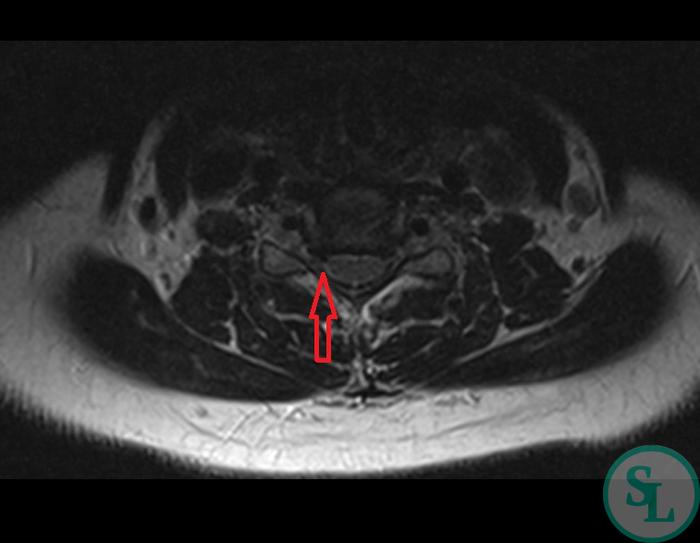

Для диагностики грыжи межпозвонкового диска C5-С6 врач может назначить магнитно-резонансную томографию (МРТ), которая позволяет получить детализированное изображение и оценить состояние межпозвонковых дисков и окружающих тканей. Ранняя диагностика и терапия помогут избежать развития более серьезных осложнений.

Согласно рассказам пациентки и данным медицинской документации, боли в области шеи беспокоят её уже довольно долго. Постепенно они стали хроническими, и не поддаются облегчению с помощью ненаркотических противовоспалительных средств (НПВС). Консервативное лечение не дало результата. В 2022 году было проведено МРТ шейного отдела позвоночника, которое показало дегенеративные изменения. Выявлена грыжа межпозвонкового диска на уровне C5-C6 с образованием стеноза и сильным сжатием нервных структур.